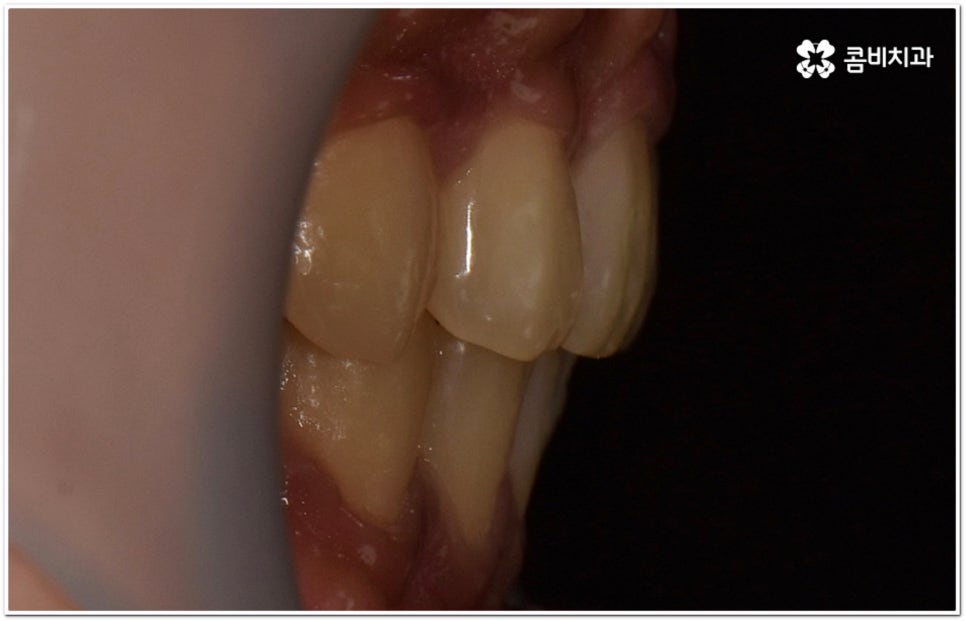

옆에서 봤을 때 코나 턱보다 입이 더 튀어나와 있으면 뾰루퉁한 인상을 줄 수 있고 웃을 때 잇몸이 드러나 콤플렉스처럼 느껴질 수 있는데요. 정도가 심한 경우 입을 꼭 닫고 있기 어려워 자기도 모르게 구호흡을 하게 되면서 여러 구강 질환 및 구취를 유발하게 될 수도 있기 때문에 이러한 심미적 또는 기능적인 이...

옆에서 봤을 때 코나 턱보다 입이 더 튀어나와 있으면 뾰루퉁한 인상을 줄 수 있고 웃을 때 잇몸이 드러나 콤플렉스처럼 느껴질 수 있는데요. 정도가 심한 경우 입을 꼭 닫고 있기 어려워 자기도 모르게 구호흡을 하게 되면서 여러 구강 질환 및 구취를 유발하게 될 수도 있기 때문에 이러한 심미적 또는 기능적인 이유로 돌출입교정치과 를 알아보시는 분들이 많이 있을 거예요.